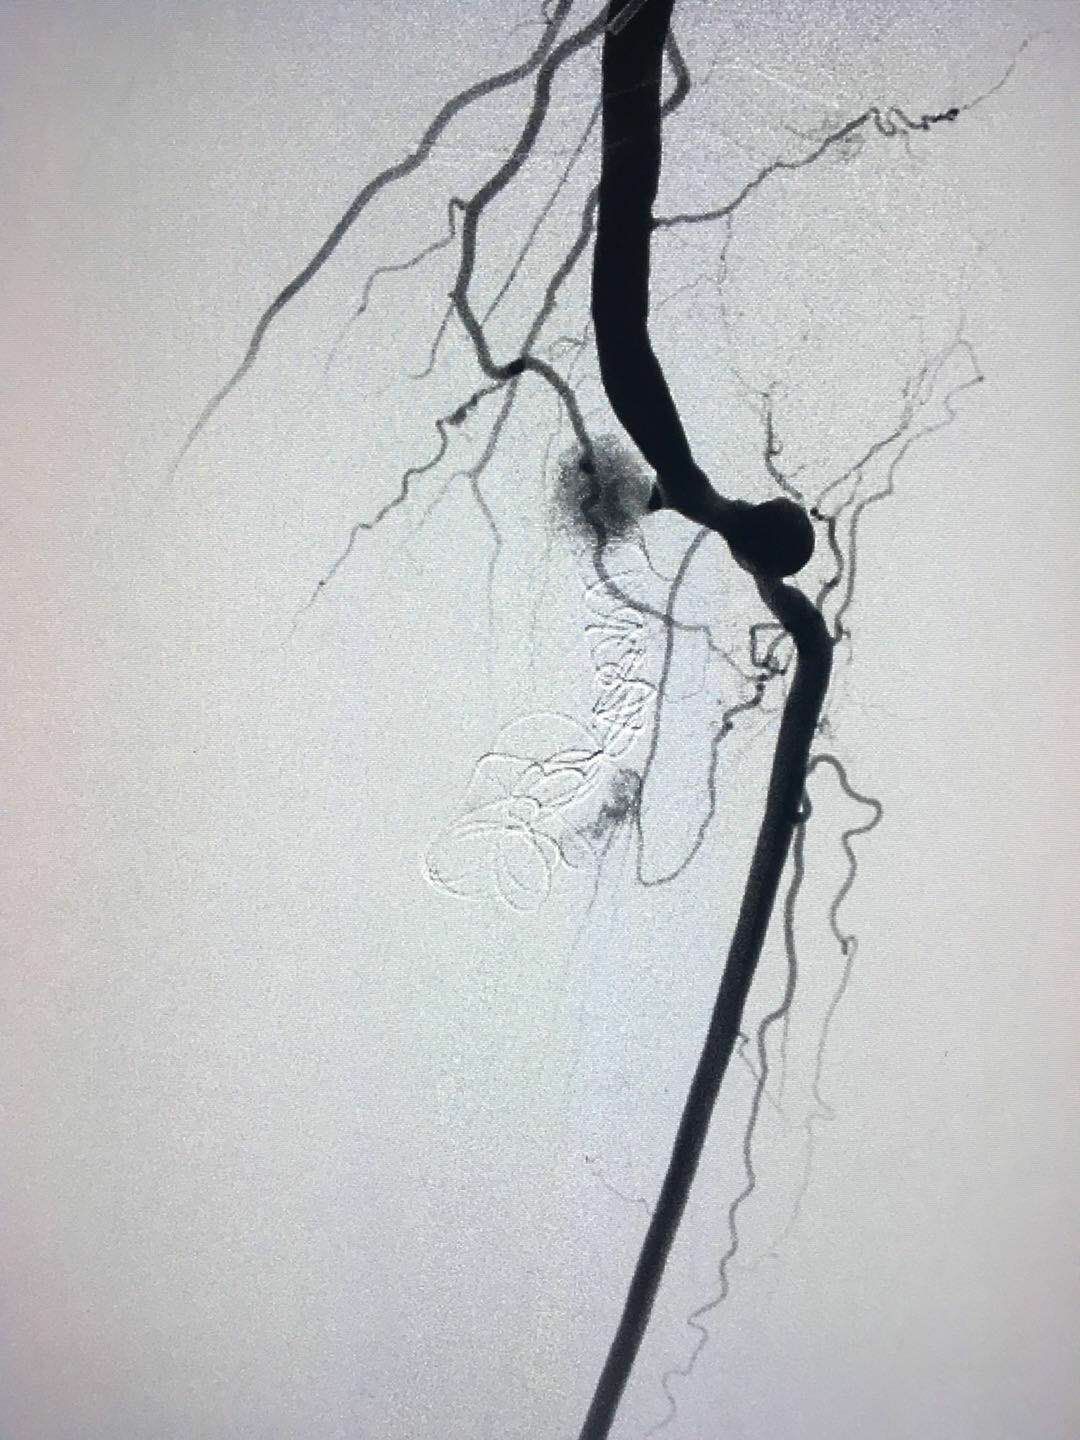

圖3:介入栓塞后瘤體及瘺消失

該例瘤體及瘺口巨大,實屬少見。介入栓塞手術(shù)難度及風險較大。難度主要是介入手術(shù)方式及栓塞劑的合理選擇;風險主要是載瘤動脈及引流靜脈的異位栓塞。我們超選擇性插管,先后選擇三種不同規(guī)格的彈簧圈栓塞,手術(shù)順利,效果良好,隨訪無并發(fā)癥發(fā)生。